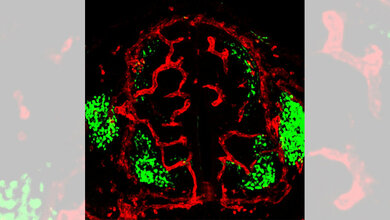

DZHK-Wissenschaftlerin Professor Dr. Stefanie Dimmeler und ihre Kollegen am Institut für kardiovaskuläre Regeneration der Goethe-Universität Frankfurt haben deshalb das Schicksal einzelner Zellen der innersten Gefäßschicht, der Endothelzellen, während der Entwicklung und nach Gewebeschädigungen in sogenannten Confetti-Mäusen untersucht. In diesen Tieren können die Wissenschaftler mithilfe fluoreszierender Proteine bestimmte Zelltypen markieren und voneinander unterscheiden. In den verwendeten Mäusen fluoreszierten ausschließlich Endothelzellen in drei unterschiedlichen Farben. Da die Fluoreszenz auch erhalten bleibt, wenn die Zellen sich teilen, kann man so einzelne Endothelzellen und ihre „Nachkommen“ verfolgen. Damit wollten die Wissenschaftler die Frage klären, ob die Zellteilung bei der Neubildung von Blutgefäßen, wie von Zebrafischen bekannt, eher zufällig erfolgt oder ob sich bestimmte Zellen immer wieder teilen und daraus die neuen Gefäße hervorgehen.

In geschädigtem Herzgewebe nach einem Herzinfarkt konnten die Forscher beobachten, dass sich bestimmte Zellen sehr häufig geteilt hatten. Diese als klonale Expansion bezeichnete Zellteilung konnten sie auch in durch Mangeldurchblutung geschädigtem Gewebe der Skelettmuskulatur feststellen. Dafür analysierten die Wissenschaftler die Fluoreszenz der Endothelzellen in Gewebeschnitten der verletzten Bereiche. Mit 30 bis 50 Prozent war der Anteil der klonal expandierenden Zellen für die Forscher überraschend hoch. „Aber eventuell unterschätzen wir den Anteil der beobachteten klonalen Expansion sogar noch“, vermutet Dimmeler. „Denn wir haben ja keine dreidimensionale Analyse durchgeführt, sondern die leuchtenden Zellen in zweidimensionalen Gewebeschnitten bestimmt.“ Weitere Experimente zeigten außerdem, dass die durch klonale Expansion gebildeten Gefäße auch durchblutet werden und damit funktionsfähig sind.